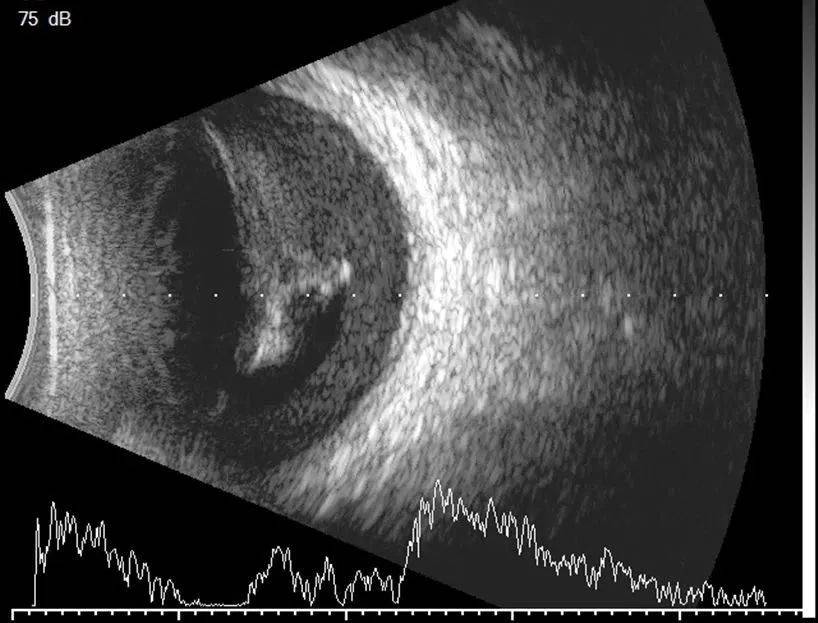

带您了解眼部b超